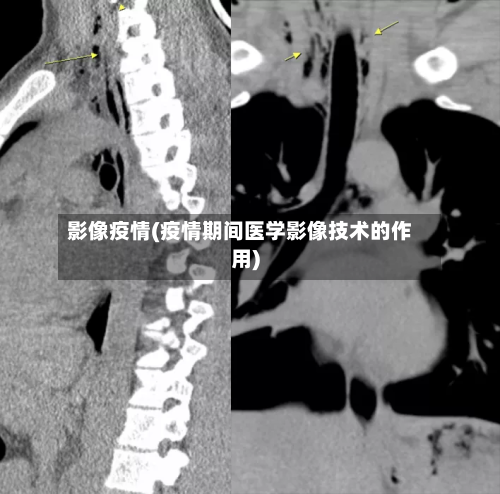

• 影像疫情(疫情期间医学影像技术的作用)

浙江省医学会放射学分会开通“新冠肺炎影像询问平台”〖壹〗、浙江省医学会放射学分会开通“新冠肺炎影像询问平台”,旨在利用互联网优势为基层医生和患者提供远程影像问诊服务,降低疫情传播风险。平台开通背景浙江省是新冠疫情仅次于湖北的高发区,各级医...